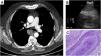

(A) Chest computed tomography confirmed the presence of a mass in the right posterior mediastinum with heterogeneous soft tissue density with punctate central calcifications in the subcarinal region. (B) Endobronquial ultrasound revealed a heterogenous mass in the subcarinal region. (C) Disordered but mature hyaline cartilage, fibrous tissue and vessels (cell block, hematoxilin–eosine, 1000×).

We present a rare case of mediastinal hamartoma diagnosed by endobronquial ultrasound-guided transbronchial needle aspiration (EBUS-TBNA). A 71-year-old man, former smoker, presented a posterior subcarinal mediastinal mass on a routine abdominal computed tomography (CT). Chest CT (Fig. 1A) confirmed the presence of a heterogenous soft-tissue density well circumscribed 3.6cm mass with punctate central calcifications. Due to its location, it was presumed to be an enlarged adenopathy, a mediastinal or pulmonary tumor, or a bronchogenic cyst. EBUS-TBNA revealed an heterogenous mass in the subcarinal region which was punctured five times (Fig. 1B). Several smears and cell blocks were obtained and cytologic diagnosis was hamartoma, with no evidence of malignancy (Fig. 1C). The patient was followed up for one year with a chest CT that did not show significant changes and he remained asymptomatic.